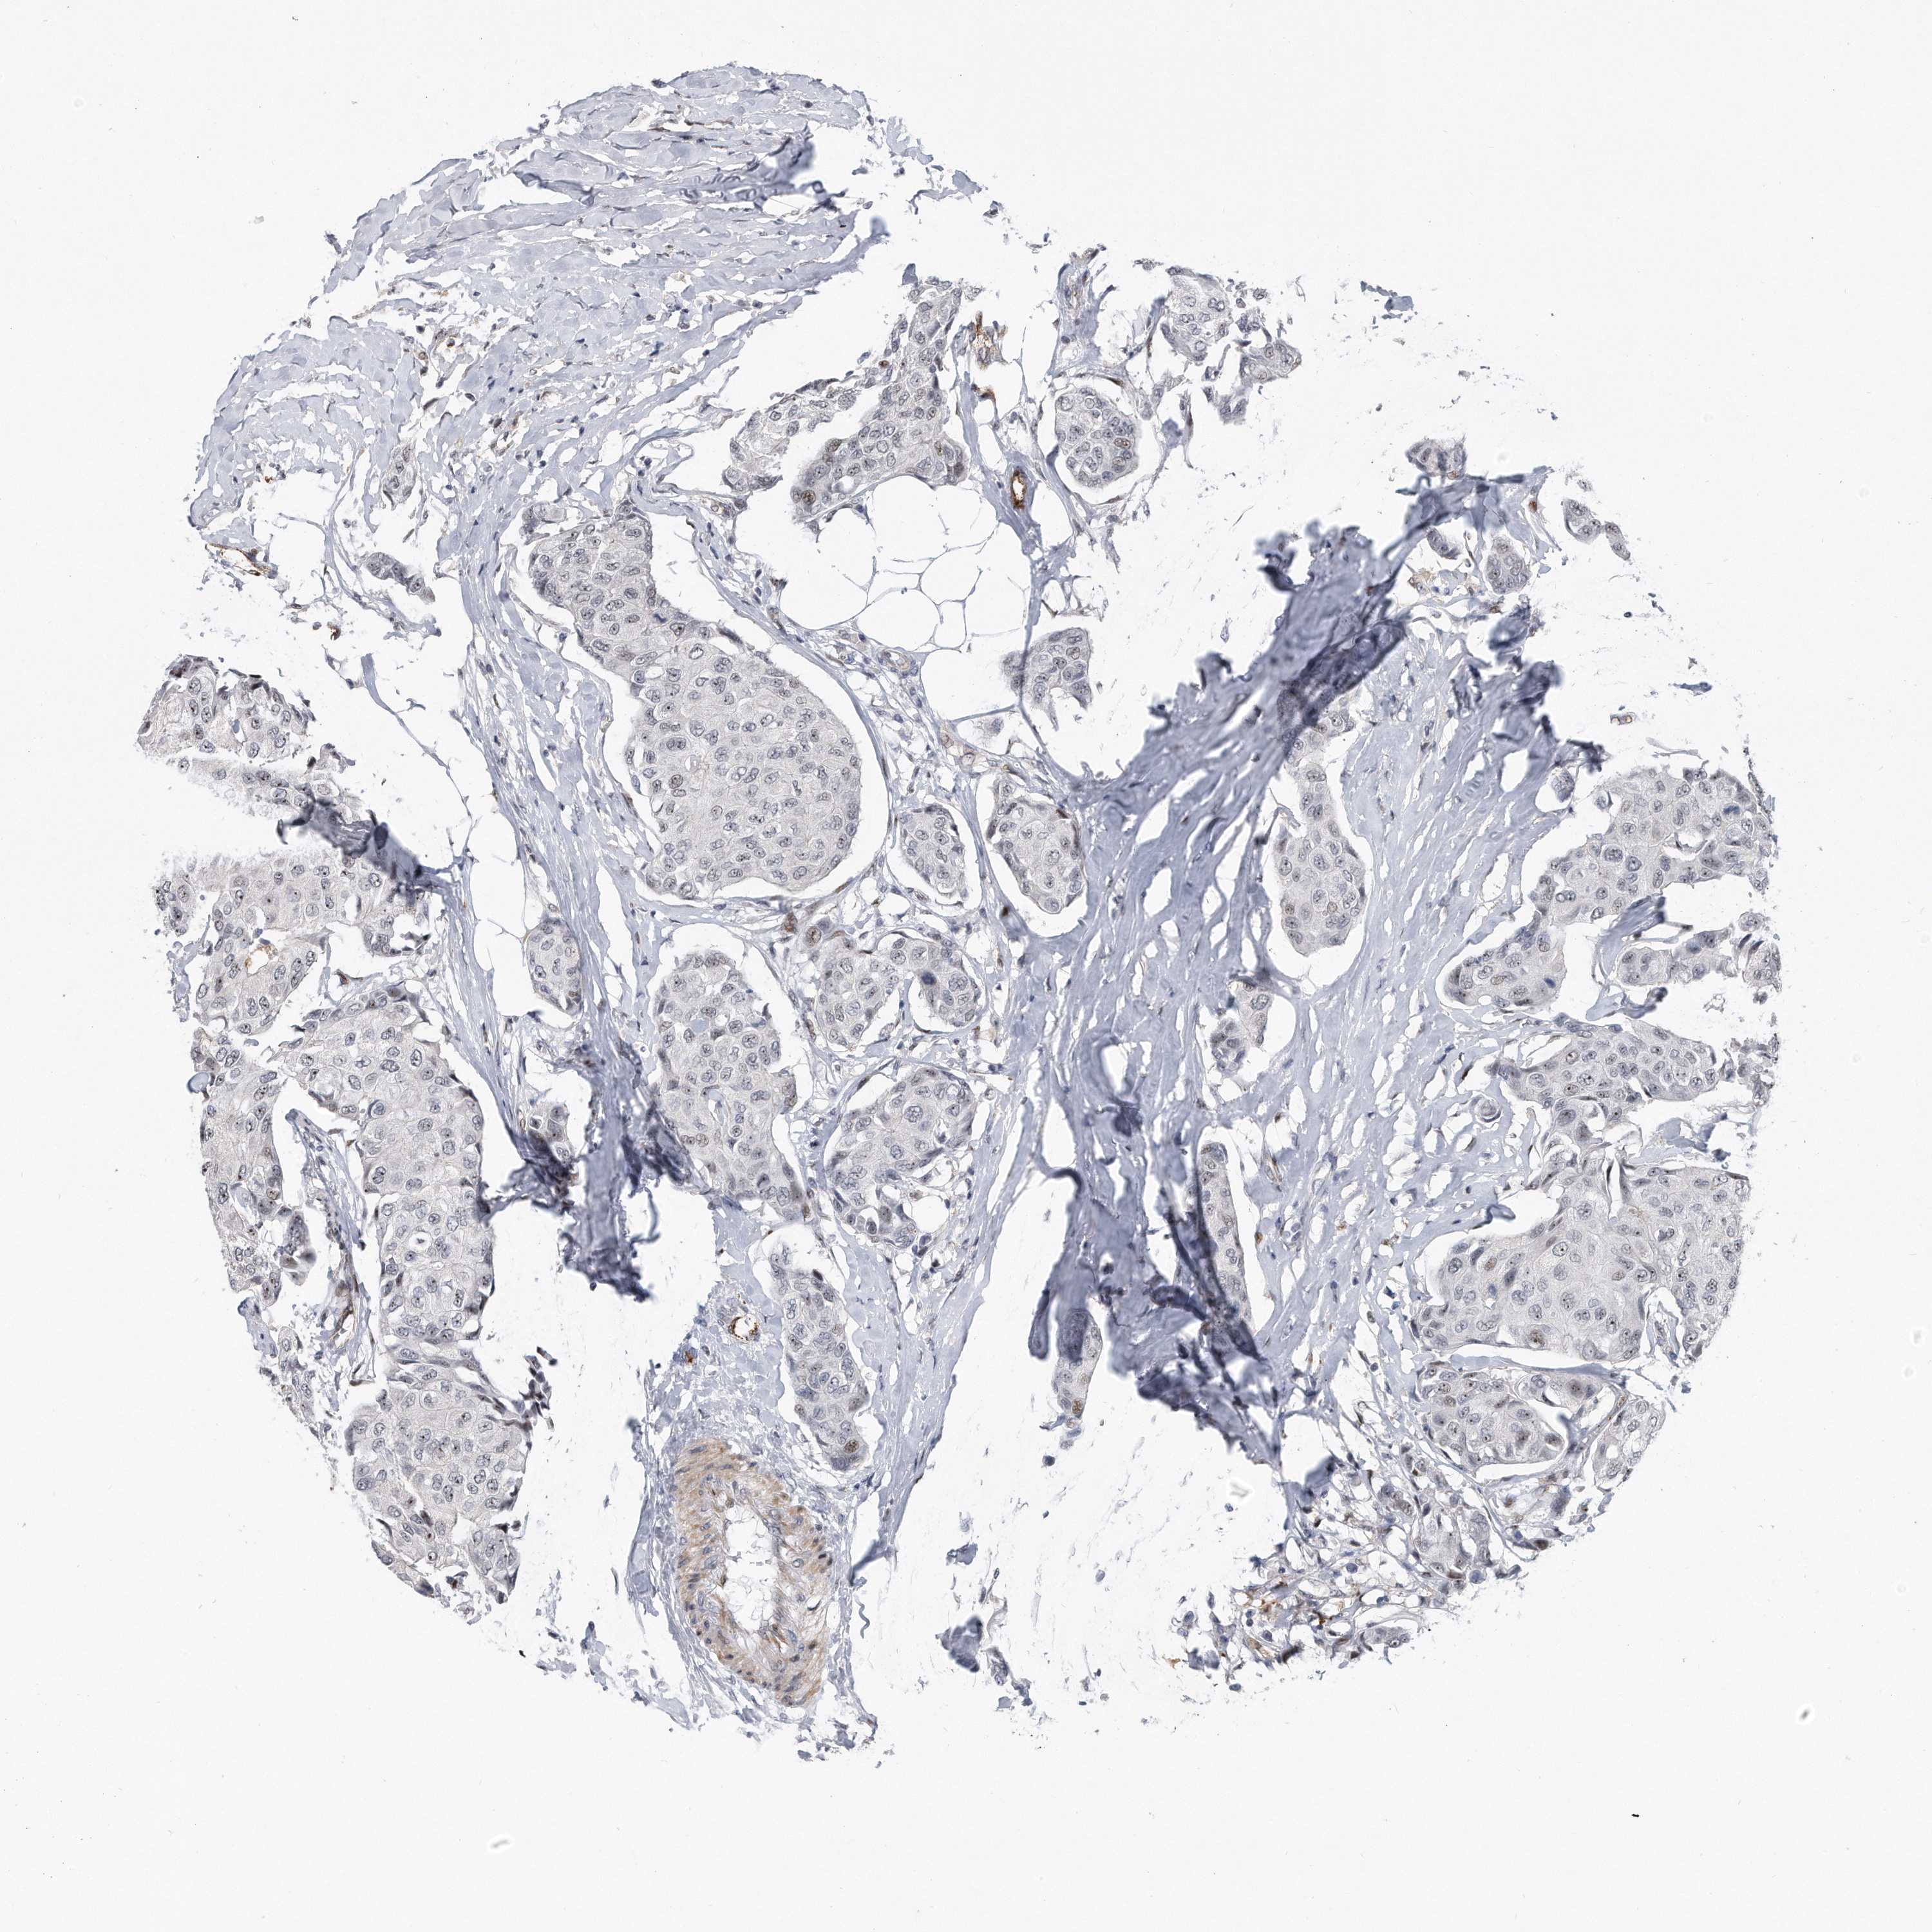

BRCA TCGA BRCA VALIDATION PROTEIN EXPRESSION

ANTIBODIES

AND

VALIDATION